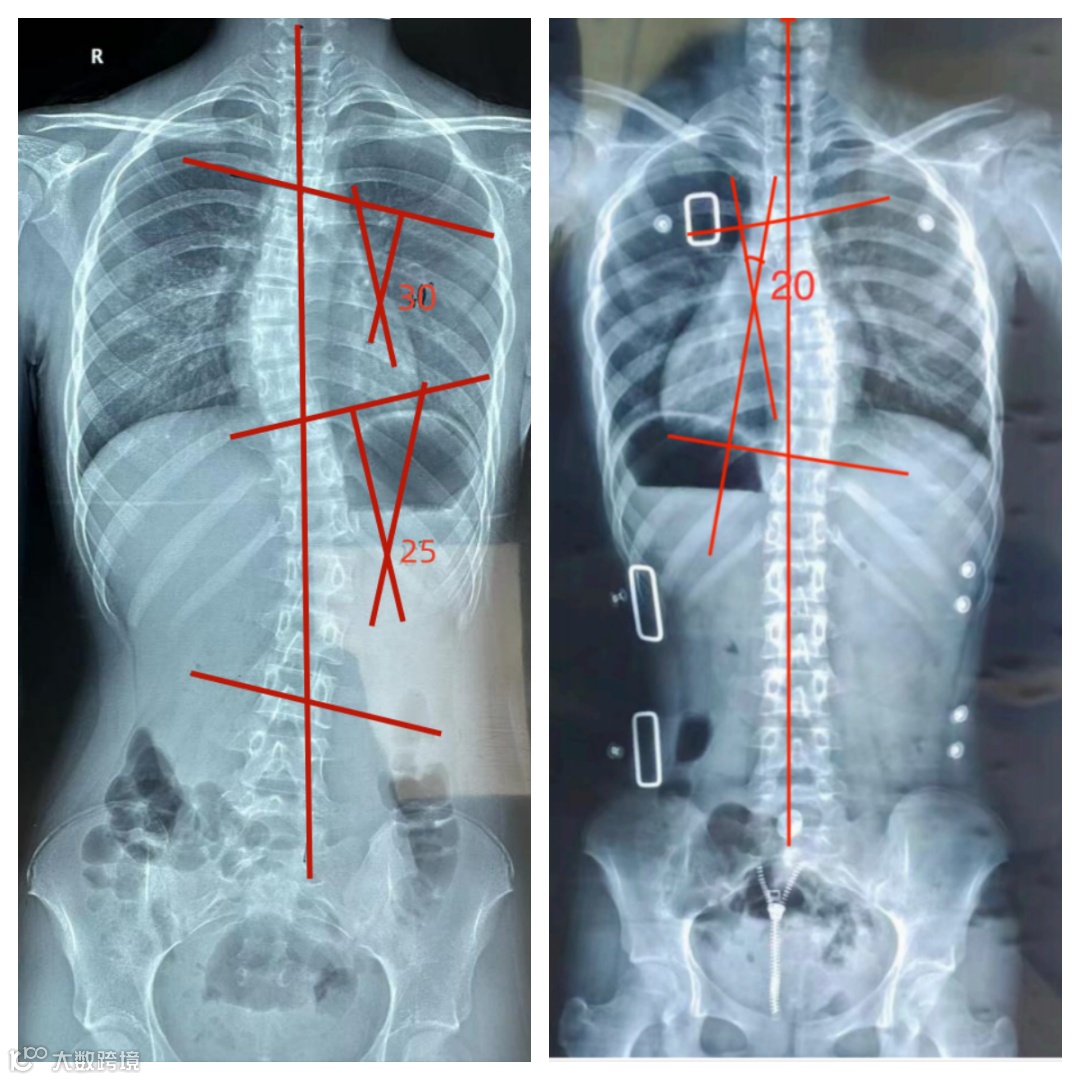

穿戴前

1:首次制作支具前评估:胸段Cobb角30°,腰段Cobb角25°,椎体旋转度Ⅲ度,ATR=胸段8°,腰段7°,Risser症Ⅳ度,高低肩明显。

2:穿上支具经过一周适应期后复查:胸段Cobb角20°,腰段Cobb角几乎为零,(因胸段侧弯位置较高,效果不如腰段,已进行调整,等待下次拍片复查看效果),椎体旋转度Ⅰ度。

穿戴后

矫正前后一周度数对比

穿戴前拍片 穿戴支具拍片

穿戴一周的对比图,患者的症状明显改善